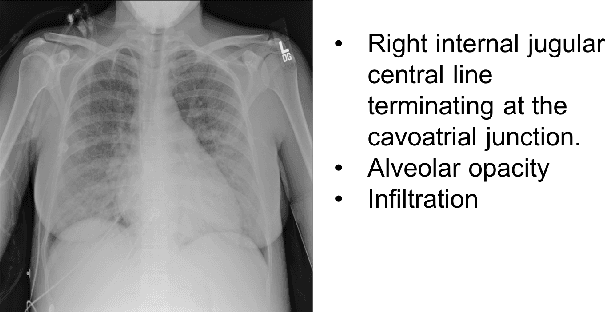

Abstract:Chest X-rays are the most common diagnostic exams in emergency rooms and hospitals. There has been a surge of work on automatic interpretation of chest X-rays using deep learning approaches after the availability of large open source chest X-ray dataset from NIH. However, the labels are not sufficiently rich and descriptive for training classification tools. Further, it does not adequately address the findings seen in Chest X-rays taken in anterior-posterior (AP) view which also depict the placement of devices such as central vascular lines and tubes. In this paper, we present a new chest X-ray benchmark database of 73 rich sentence-level descriptors of findings seen in AP chest X-rays. We describe our method of obtaining these findings through a semi-automated ground truth generation process from crowdsourcing of clinician annotations. We also present results of building classifiers for these findings that show that such higher granularity labels can also be learned through the framework of deep learning classifiers.